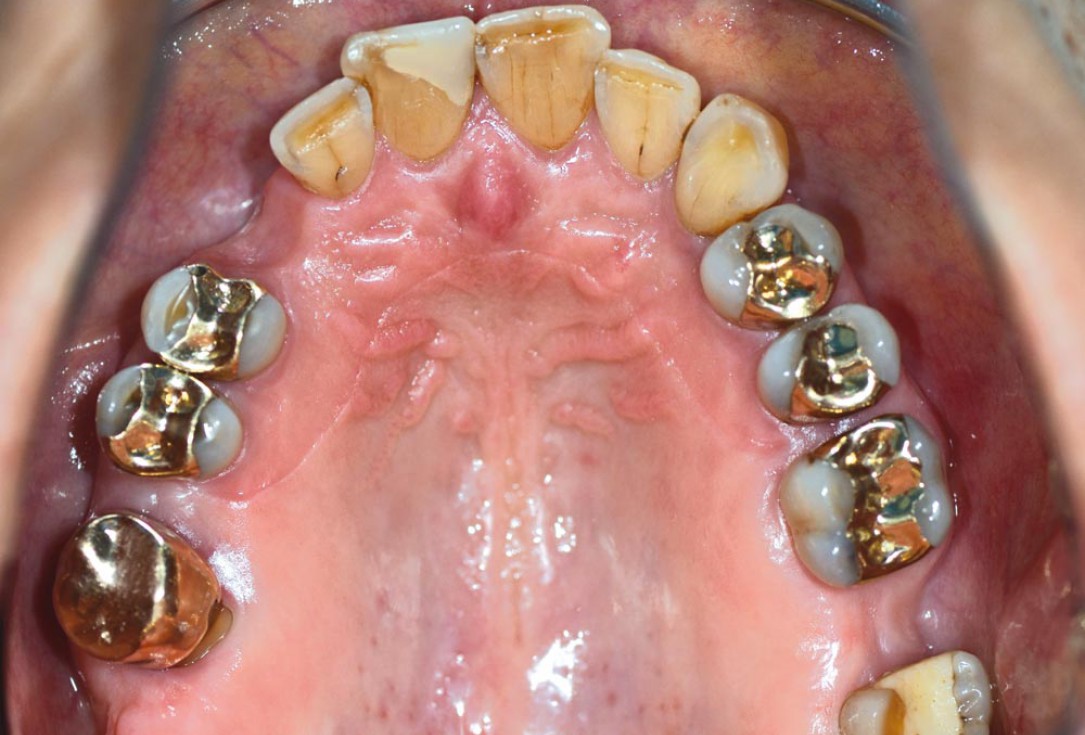

02/12 - Occlusal view of initial situation

Block augmentation with maxgraft® in the maxilla - PD Dr. Dr. F. Kloss

11/12 - Final clinical situation

12/12 - Stable situation 12 months after final prosthesis